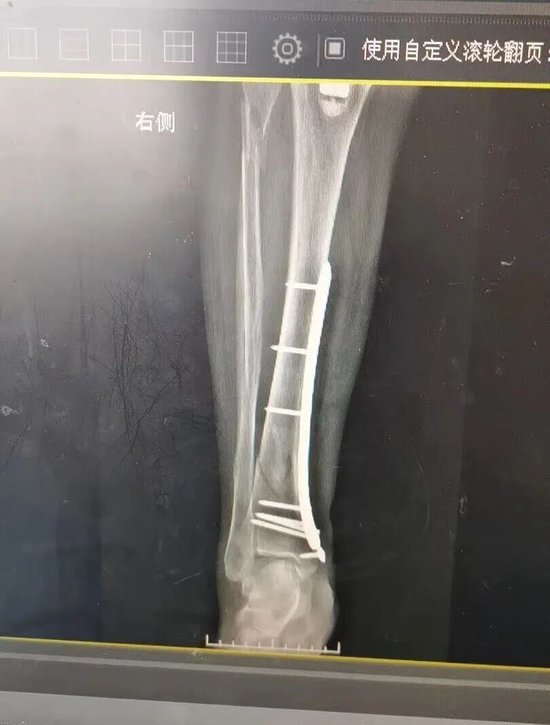

手术由杜明主任主刀,倪守洋、冯志强医师协助进行。在硬膜外麻醉后,团队经患者右侧小腿切口,精准清除病灶,明确为胫骨远端螺旋型骨折。术中,团队顺利复位骨折端,先以3枚克氏针临时固定;在透视确认对位良好后,再置入胫骨远端钛板与皮质骨螺钉,实现牢固固定。整个过程顺利,患者生命体征平稳。

术后,科室护理团队无缝衔接,为相女士制定了详细的康复计划,密切监测其伤口愈合、肢体功能恢复情况,并根据恢复进度及时优化调整治疗方案,全力保障患者顺利康复。